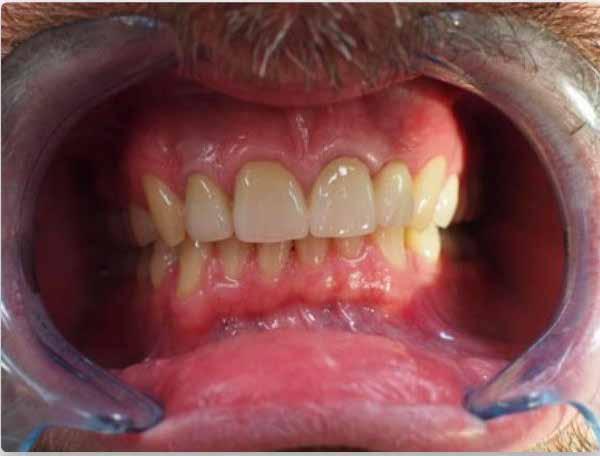

Esetbemutatás

Egy 37 éves nőbeteg jelentkezett dr. Takayama fogászati rendelőjében frontfogai színének és formájának korrekciója és ínygyulladása kezelésének céljából. A 23-as fogát még iskoláskorában távolították el, és ezen a területen ínyrecesszió volt látható. A páciens a 21-es fogtól a 24-es fogig terjedő híddal, valamint 11-es és 12-es szólókoronákkal rendelkezett, amikor először érkezett a rendelőbe. Különösen a híd formája nem felelt meg az esztétikai igényeinek (1-2. ábra).

Tervezés és előzetes kezelések

Az adott körülmények miatt a porcelán rétegezéséhez labiálisan nem állt rendelkezésre elegendő hely. Ezért úgy döntöttünk, hogy a monolitikus fogpótlást Zolid Gen-X Multilayerből (Amann Girrbach) készítjük el, amely egy rendkívül transzlucens és polikromatikus cirkónium-dioxid; illetve a labiálisan dőlt és torlódott alsó frontfogak részleges fogszabályozását is elvégezzük.

A marginális gingiva korrekcióját még a helyreállító kezelés előtt el kellett végeznünk. Az ínygyulladás és a 23-as fog hiánya miatt az íny jelentősen visszahúzódott e régióban. Ezt műtéti úton korrigáltuk, hogy később természetes marginális ínyszélt érjünk el (3-4. ábra). Az előzetes kezeléseket követően (5-6. ábra) a fogorvos előkészítette a fogakat az új fogpótláshoz (7. ábra).

Eredmények

Jelen esetben a fogak helyzete limitációt jelentett a koronák vastagságát illetően, mivel nem volt hely a kerámia rétegezésére. A szemfogakat bevonó fronthidaknak erősnek és esztétikusnak kell lenniük. Ilyen esetekben a Zolid Gen-X a legjobb anyag, mert szilárdságot és esztétikát kínál. Ezenkívül a Zolid Gen-X és a Ceramill M-Smile kombinációja a front monolit koronák gyártásakor rendkívül esztétikus eredményt hozott (35. ábra) . A páciensnek gyönyörű mosolya lett a front monolitikus cirkónium-dioxidból készült restaurációk beragasztása után (36. ábra).